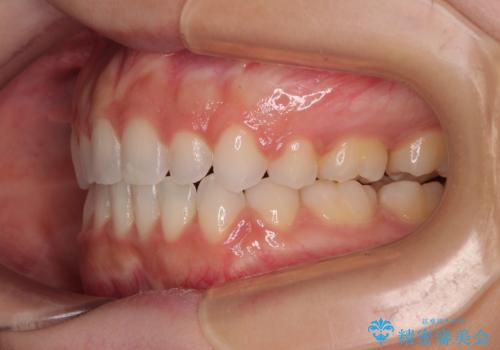

- 前歯のデコボコとクロスバイトを気にして来院された患者様です。

上下ともにデコボコはそれほど強くありませんでしたが、非抜歯では口元が突出した仕上がりとなる可能性があるため、上下左右の第一小臼歯4本を抜歯し、ワイヤー装置での抜歯矯正を行うこととしました

スペースを閉じるために期間を要しましたが、無事に綺麗な口元に仕上げることができました。